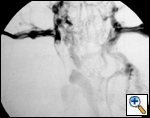

| Figure 4. Superior vena cavography showing obstruction by a mediastinal tumor. |

The preoperative work–up should always include total body CT scan for patients with lung cancer or tumors of the mediastinum. Other specific investigations should be tailored according to the histological diagnosis. Superior vena cavography should be performed when SVC invasion is suspected (Figure 4). Alternatively, magnetic resonance imaging can help to define the site and extension of the infiltration and the presence of thrombosis, and anatomical variations of the SVC system can be revealed. Echocardiography should be routinely included to rule out extension of a thrombus into the right atrium. Brain CT scan with contrast injection should always be performed for staging purposes (lung cancer) and also to rule out the presence of any brain disease that may be exacerbated by CNS edema during SVC clamping.